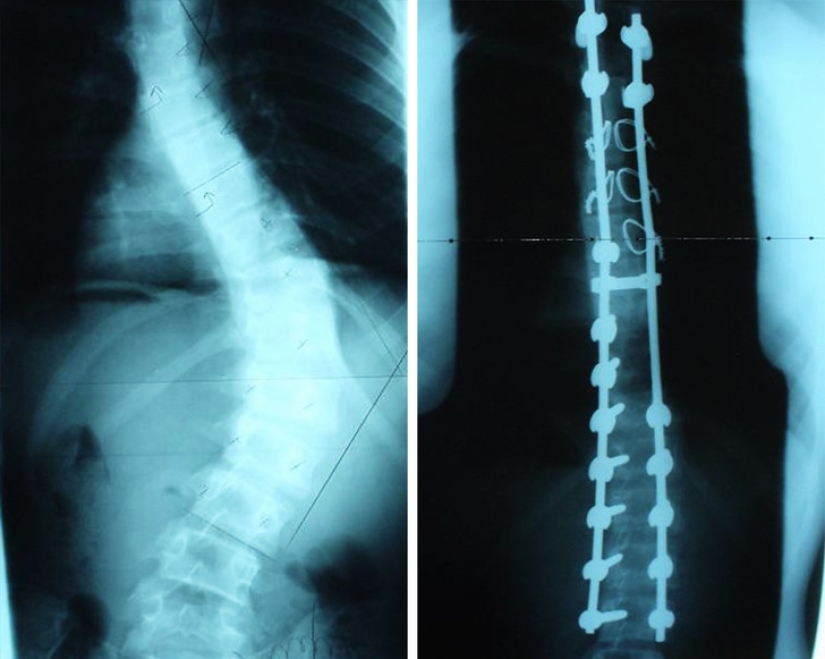

X-ray before and after surgery to correct scoliosis.